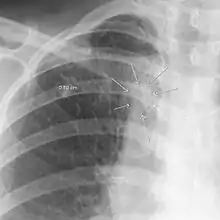

| The arrows denote an ill-defined nodular opacity in medial aspect of right upper lobe with ill-defined rim of lucency surrounding it | |

| Differential diagnosis | Aspergilloma |

In radiology, the air crescent sign is a finding on chest radiograph and computed tomography that is crescenteric and radiolucent, due to a lung cavity that is filled with air and has a round radiopaque mass.[1] Classically, it is due to an aspergilloma, a form of aspergillosis, that occurs when the fungus Aspergillus grows in a cavity in the lung.[2] It is also referred as Monad sign.[3]